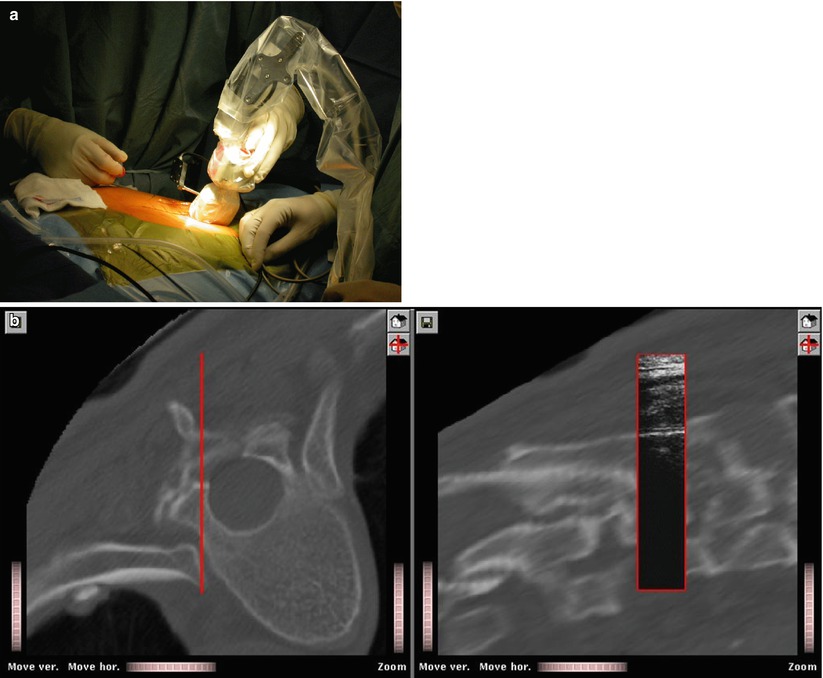

From scan4dent.com

Ortho File Scan4Dent Ortho Or Radiology Based on our study, orthopaedic providers are significantly faster, more accurate, and make fewer mistakes affecting patient care while. Understanding the basis of the imaging modalities available to diagnose many commonly encountered disorders of the bones and joints is of utmost importance. Unless you do ir, your radiation exposure will likely be higher in ortho than in diagnostic radiology due. Ortho Or Radiology.